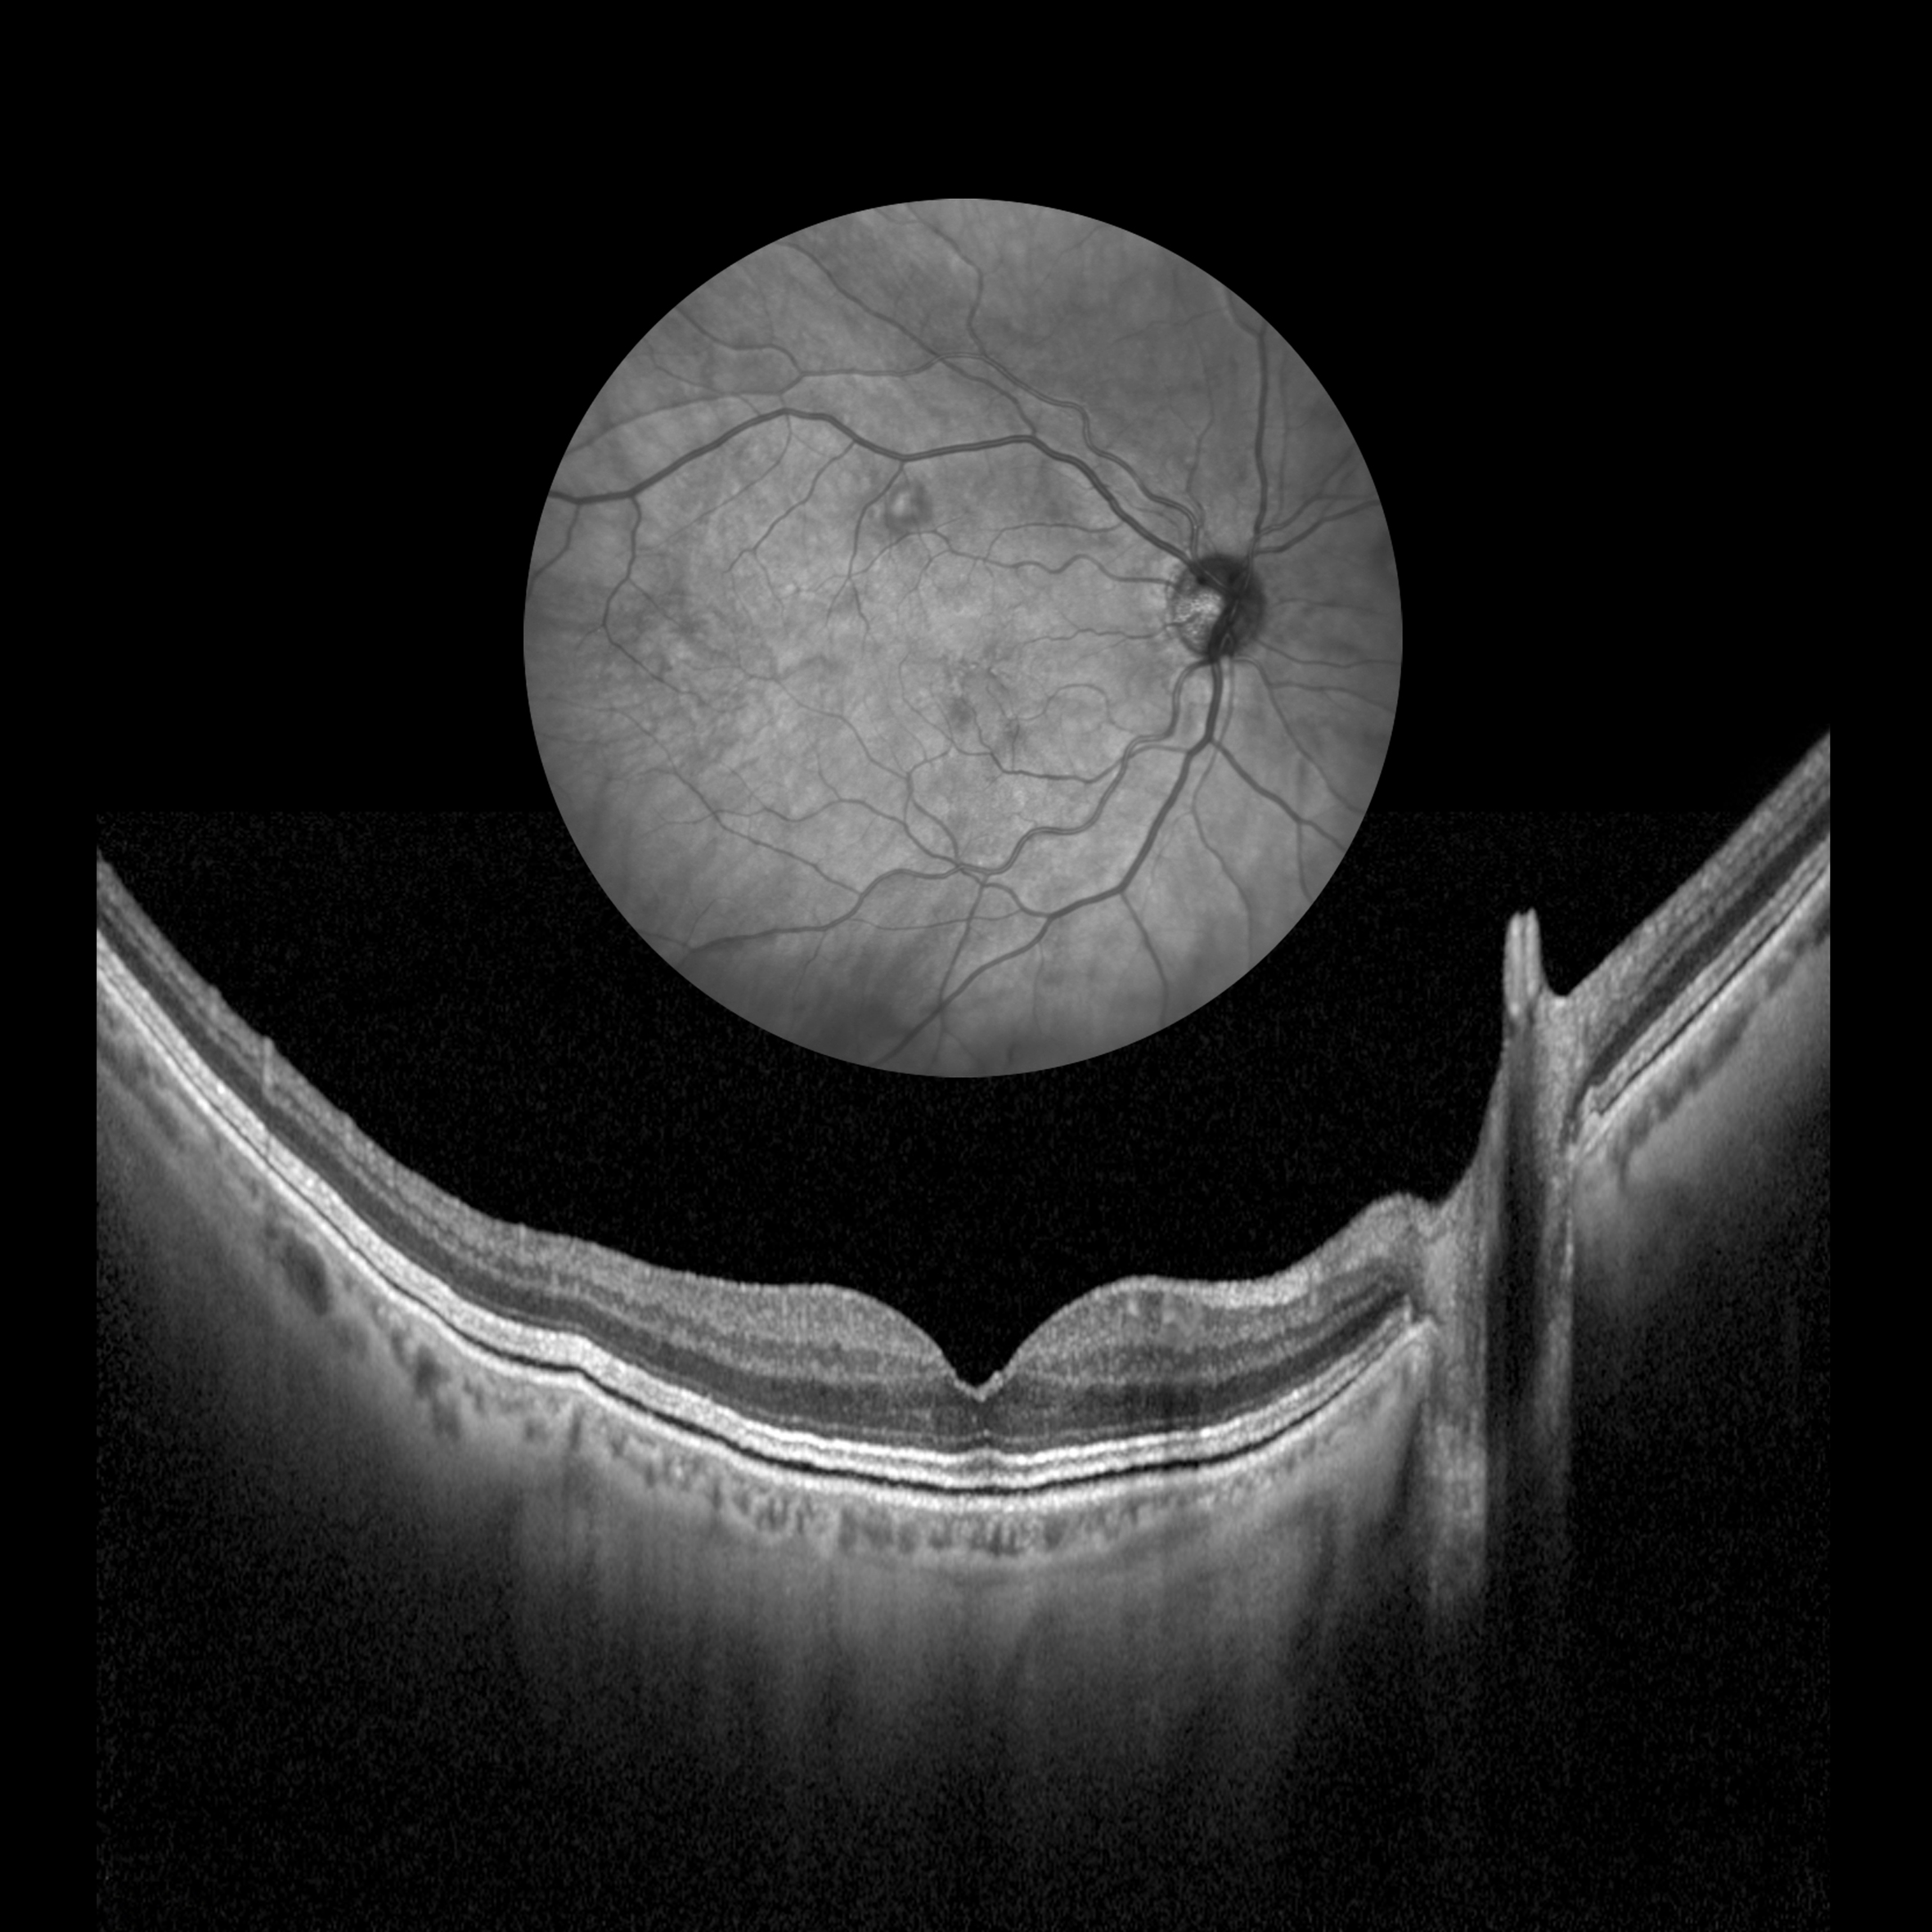

Retinopathy OCT Presented by Barbara Klemenc This photograph received Second Place, Ocular Coherence Tomography in the 2025 OPS Scientific Exhibit. Filed Under Retina OPS Photo